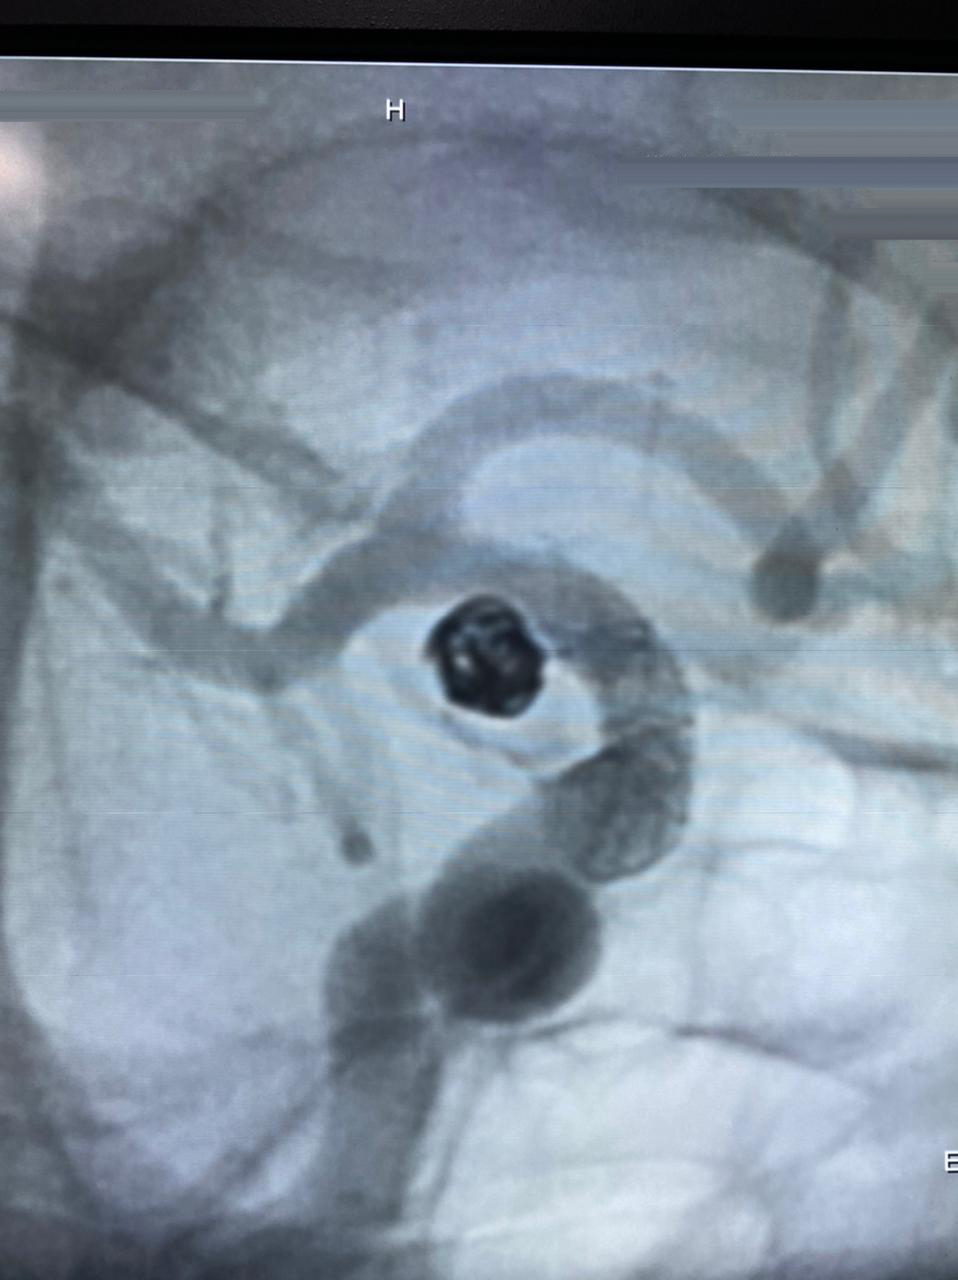

HCorBJ realiza procedimento de Embolização de Aneurisma Cerebral

O procedimento de Embolização de Aneurisma Cerebral é realizado no Setor de Hemodinâmica, sob anestesia geral, com um aparelho de imagem de última geração. O tratamento endovascular, é uma opção minimamente invasiva para as doenças cerebrovasculares.

Dr. Jivago Szpoganicz Sabatini, médico neurologista e neurorradiologista intervencionista que realizou o procedimento destaca, “esse procedimento usa uma tecnologia inovadora, trazendo excelentes resultados, usando o que há de melhor no mundo, em benefício dos pacientes neurológicos.”

“O primeiro caso de Embolização de Aneurisma Cerebral em Ponta Grossa, com stent diversor de fluxo, foi realizado no Hospital do Coração Bom Jesus em dezembro de 2018, o HCorBJ tem estrutura excelente para isso, tanto para realização do método, quanto no atendimento pós- operatório dos pacientes na Unidade de Terapia Intensiva (UTI) e enfermaria, com equipes altamente especializadas”, ressalta Sabatini.

A última intervenção realizada no HCorBJ, contou com a participação do Dr. Gelson Luis Koppe, médico neurorradiologista intervencionista de Curitiba.